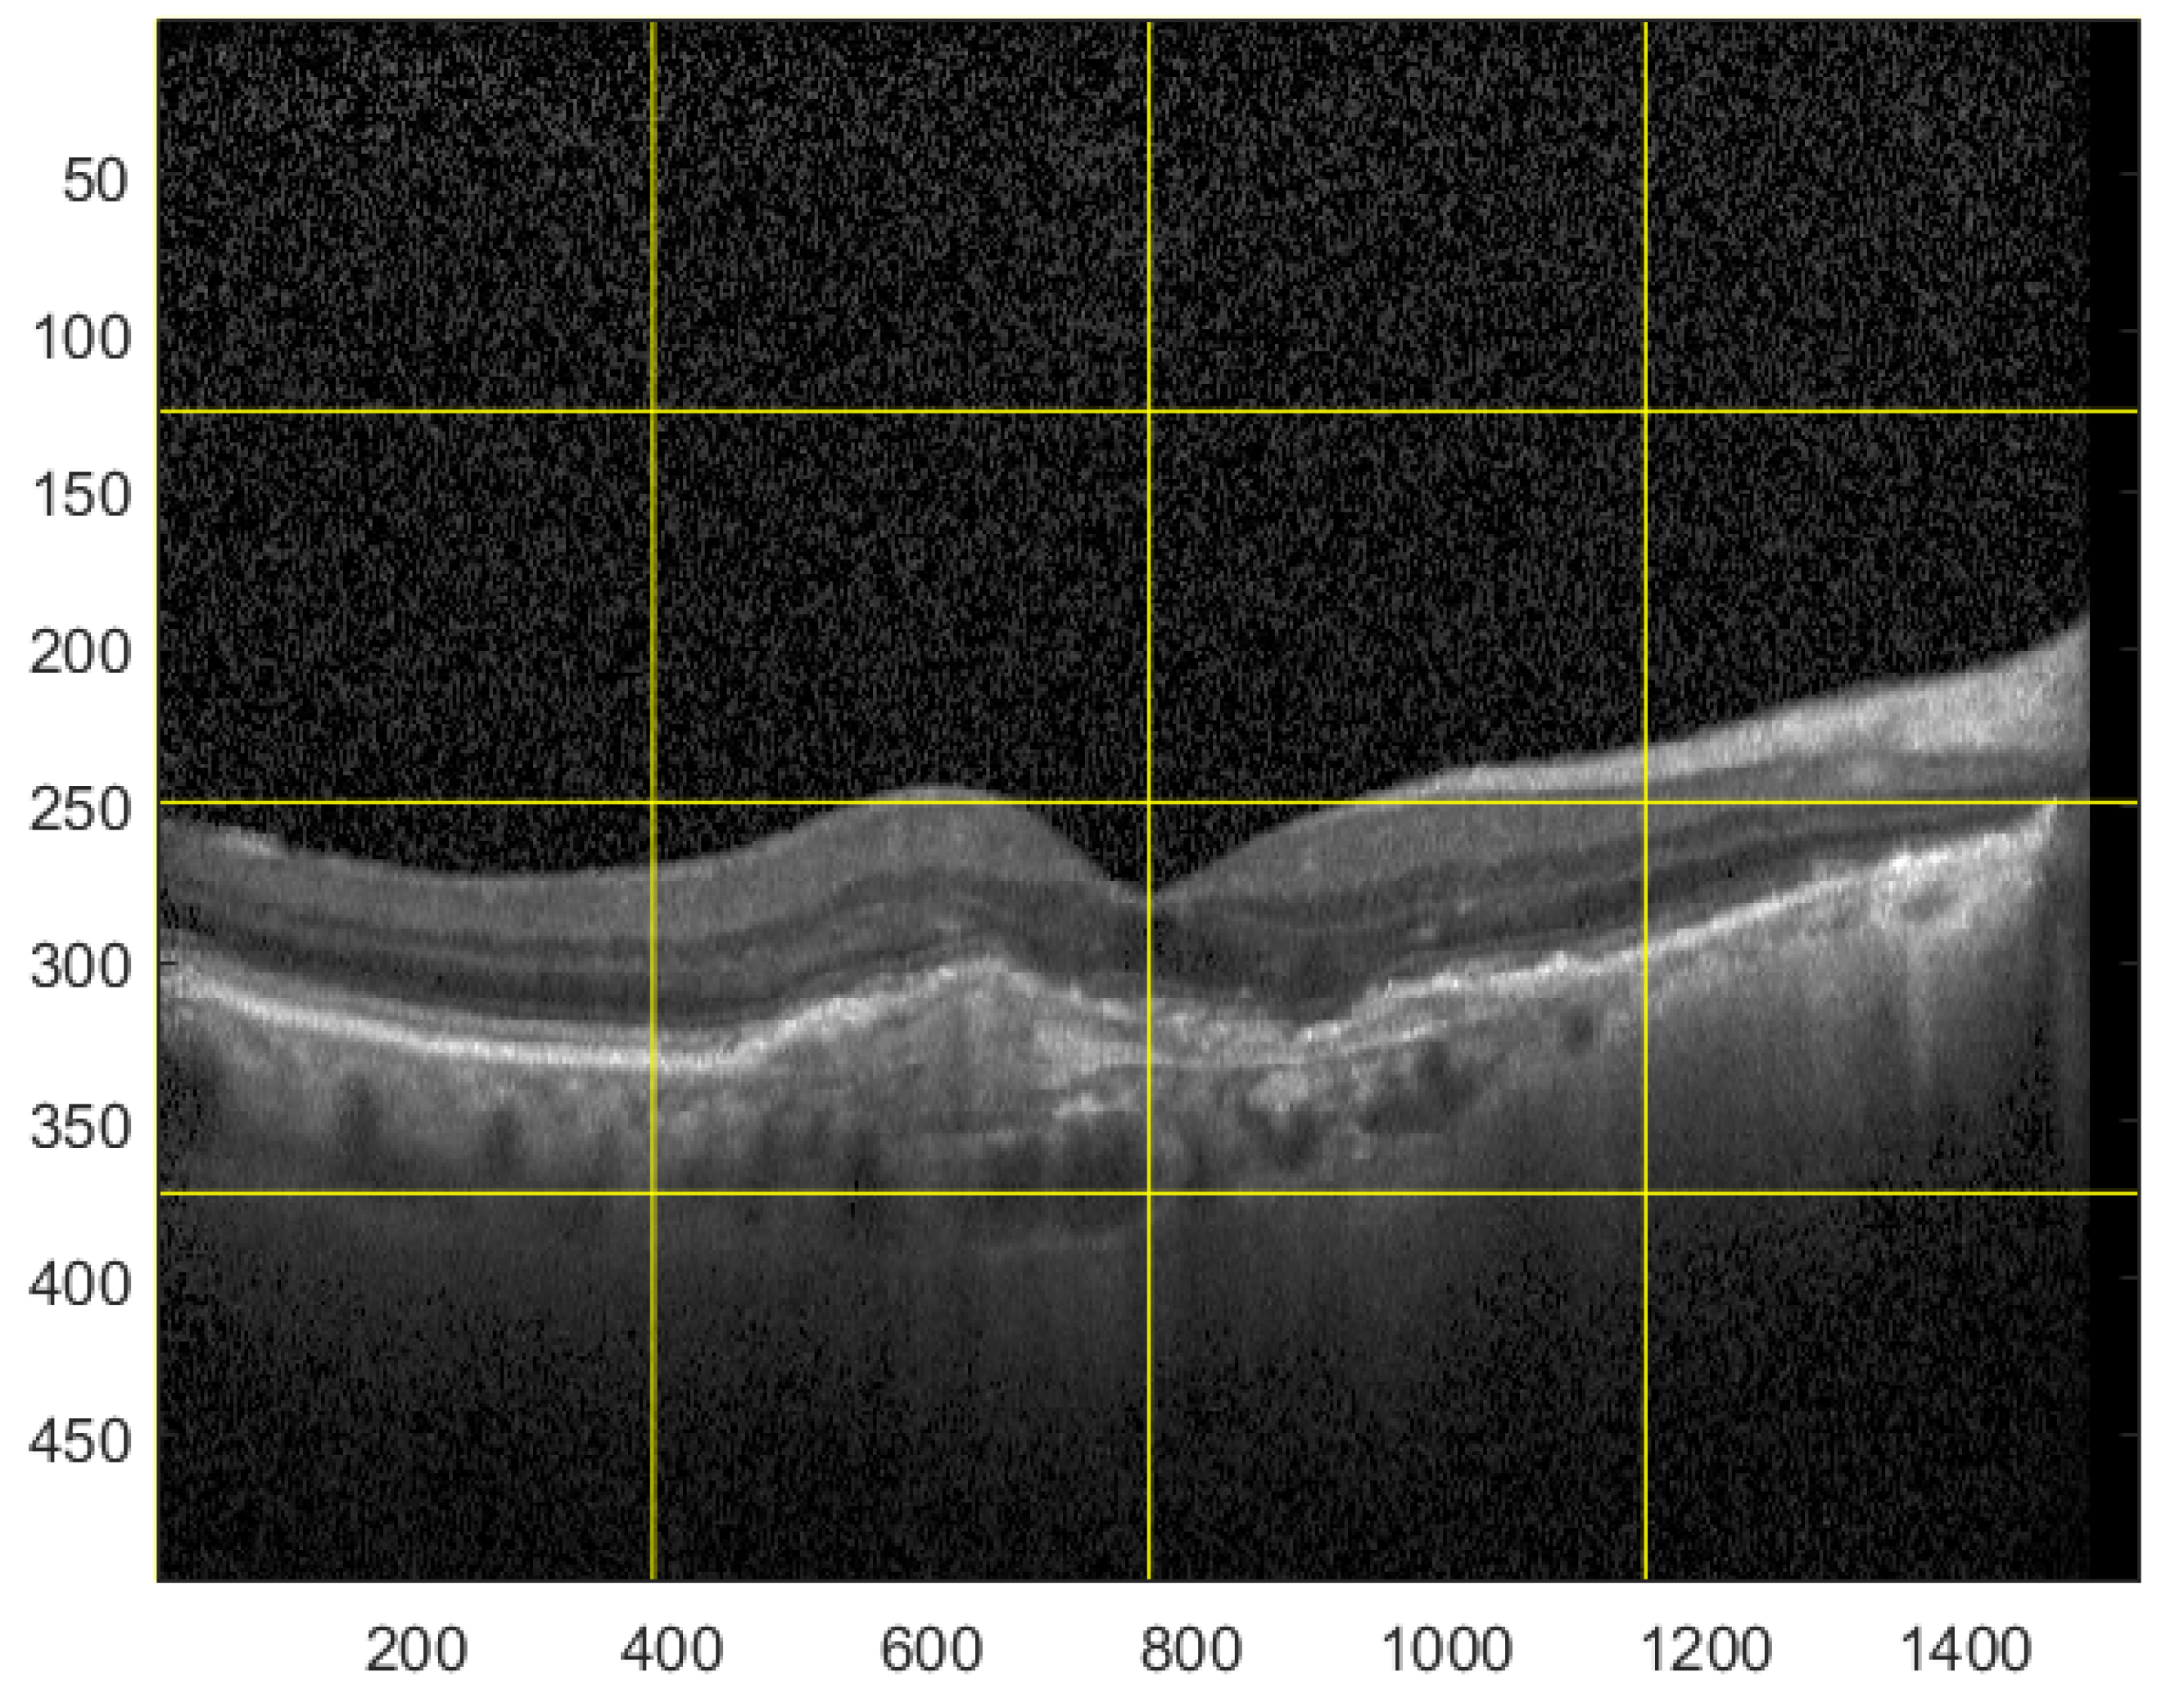

For the testing purpose and the presentation of the image manipulation detection method in the following section, the Optical Coherence Tomography (OCT) images, having the resolution of 1536 × 496 pixels, were used [33]. The OCT is a non-invasive imaging examination that uses light waves to take cross-section pictures of the human retina. One sample image of this type is shown in Figure 3. The tests show that the blocks: 37–39, 45–47, and 53–55, marked in Figure 4, should be usually selected for the process of inserting secret information. This conclusion is based on the analysis of spectra of diverse images with varying content and characteristics. For the selection of the best channel for watermark embedding, the mean of all absolute values from each block is calculated. The channel with the lowest mean is chosen as the first candidate for the subsequent data embedding operation. To increase the capacity of the watermark, other blocks can be selected afterward, considering their mean values sorted in ascending order.

Figure 3.

Sample OCT image.

Figure 4.

Blocks selected for data embedding.